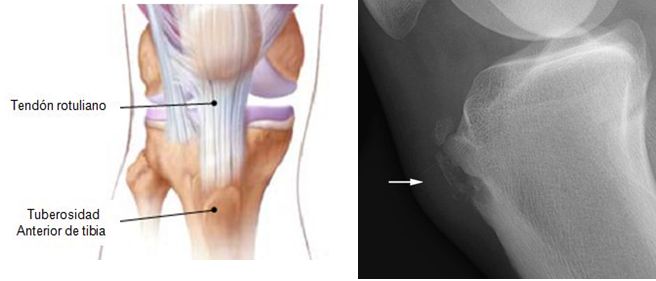

DOLOR EN MIEMBROS INFERIORES.

SEMIOLOGIA DE LOS MIEMBROS INFERIORES